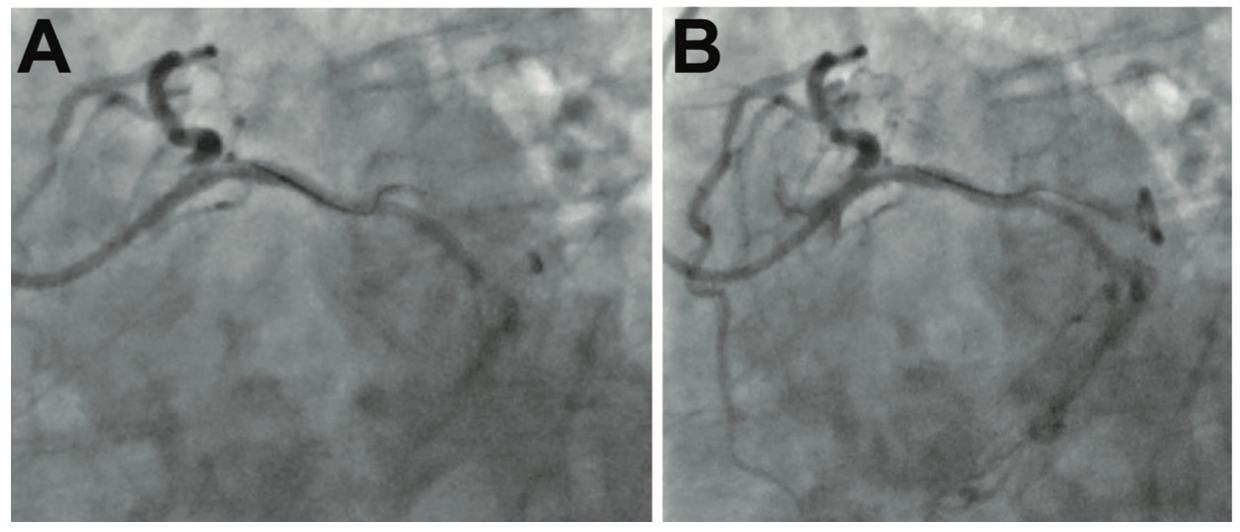

A Balance Middleweight (BMW) wire (Abbott Vascular), followed by a Hi-Torque Whisper guidewire (Abbott Vascular) failed to cross the lesion due to the severity of stenosis and the angulated take-off of the OM. The angulation was tackled with an additional curve on the Whisper wire’s tip, by itself and then in combination with a 90-degree angled SuperCross microcatheter (Teleflex). The Hi-Torque Whisper wire was able to enter the ostium of the OM by parking the microcatheter with its tip parallel to the ostium; however, it still failed to cross the lesion. The tip would enter the lesion and then buckle and bounce off into the main circumflex due to the severity of stenosis, which appeared to be 100% (Figure 1, Video 1). The presence of brisk antegrade flow in the OM distal to the stenosis was convincing for an invisible microchannel available across the occlusion; therefore, we decided to utilize the ability of the fluid contrast agent to find the microchannel. We positioned the wire at the occlusion and injected 10 cc of contrast with high manual pressure, effectively replacing the blood in the microchannel with the lower viscosity contrast agent, and captured the scene under cine angiography. At this time, the wire was inside the SuperCross microcatheter, which allowed the wire to float inside the microcathether without resistance by the Copilot Bleedback Control valve (Abbott Vascular), which was tight around the microcatheter. Simultaneous to contrast agent injection by the assistant, the operator advanced the wire very slowly and let the wire float itself, along with the contrast agent, across the uncrossable microchannel into the distal OM1 (Figure 2A-B, Video 2). The proposed mechanism is the replacement of red blood cells (RBC) by the contrast media mixing with blood. Once the wire crossed the lesion, the rest of the case was expeditiously completed with angioplasty and stenting of the OM.